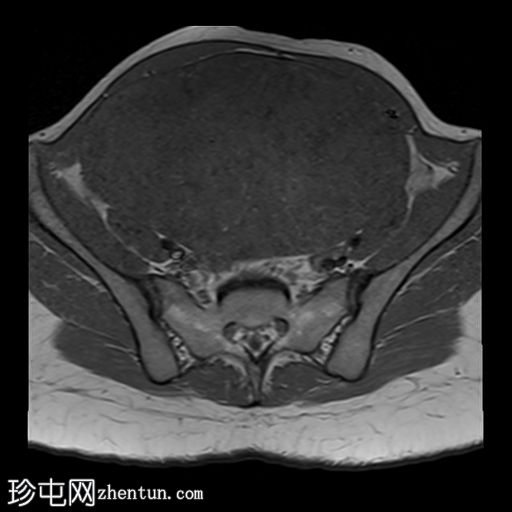

MRI

轴向

T1

子宫后壁可见一个边界清晰、体积较大的浆膜下肌瘤,大小约为16.1 x 10.5 x 14.4 cm(宽 x 深 x 高)。

该肌瘤在T1加权像上呈中等信号,在T2加权像上呈低信号,内部区域呈囊性变性。

该肿块导致正常子宫结构严重变形。增强扫描显示轻度不均匀强化,未见弥散受限征象或提示恶性肿瘤的可疑强化。